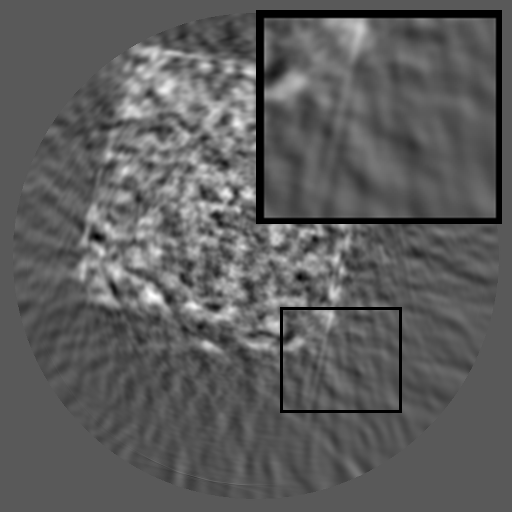

Figure 3: Visual comparison on TomoBank and LoDoPaB under random masking (ratio = 0.8). Rows 1 and 3 show the inpainted sinograms, while Rows 2 and 4 present the corresponding FBP (Ramachandran and Lakshminarayanan, 1971)-reconstructed images.

Table 1 summarizes the quantitative performance of FCDM and all baselines on the TomoBank and LoDoPaB datasets under both random and periodic masks. Figure 3 presents qualitative comparisons at a mask ratio of 0.8, showing both the inpainted sinograms and the reconstructed images obtained using FBP (Ramachandran and Lakshminarayanan, 1971). Across all settings, FCDM consistently achieves the highest SSIM and PSNR values, demonstrating its strong capability in recovering structural details and suppressing noise-induced artifacts. Visual results in Figure 3 further confirm that FCDM produces smoother and more consistent sinograms, while other methods often exhibit angular streaking or local inconsistencies.